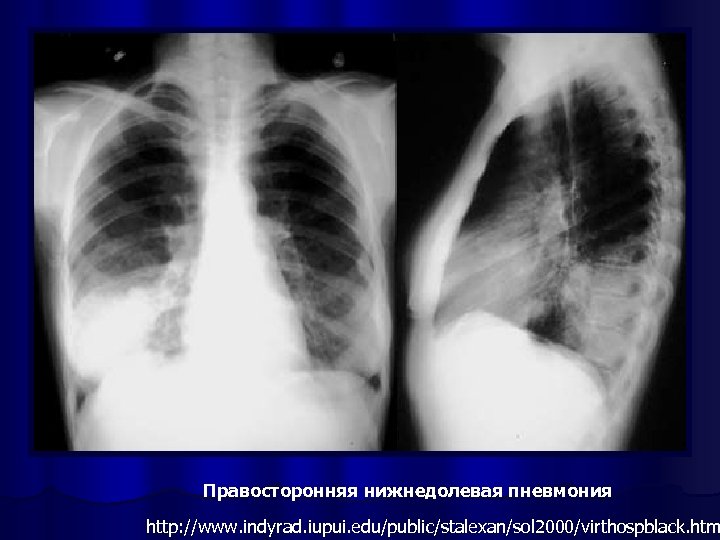

Правосторонняя нижнедолевая пневмония http: //www. indyrad. iupui. edu/public/stalexan/sol 2000/virthospblack. htm

Рентгенография органов грудной клетки l обязательный метод исследования при пневмонии, l позволяет визуализировать пневмонический инфильтрат, l оценить динамику процесса, l распространённость инфильтрации, наличие плеврального выпота, признаков деструкции лёгочной ткани отражают тяжесть заболевания и определяют тактику лечения.

Рентгенологическое исследование проводится в начале заболевания и не ранее чем через 14 дней после начала АБТ; может быть выполнено и в более ранние сроки при возникновении осложнений или существенном изменении клинической картины заболевания l в практической работе полноформатная пленочная рентгенография часто заменяется крупнокадровой флюорографией или цифровой флюорографией, которая в этих случаях выполняется в аналогичных проекциях l в типичных случаях ВБП критерий диагноза - обнаружение очагово-инфильтративных или интерстициальных изменений в легких l

ОБЯЗАТЕЛЬНО В ДИАГНОСТИКЕ ПНЕВМОНИИ: 2 проекции!!!

Рентгенологическая картина ВП l Основной рентгенологический признак ВП - локальное снижение воздушности легочной ткани (инфильтрация) за счет накопления воспалительного экссудата в респираторных отделах. l Рентгенологическая и КТ картина ВП определяется типом инфильтрации легочной ткани и стадией воспалительного процесса.